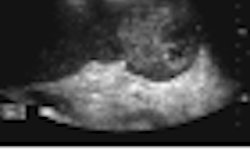

1 avril 2012 -- Observation: Femme admise pour des douleurs dans le quadrant supérieur droit de l'abdomen. Diagnostic fortuit d'une lésion splénique. Nous remercions le Dr. Anagha Parkar, Haraldsplass Diakonale Sykehus de Bergen, Norvège, d'avoir collaboré à ce cas. Cliquez ici pour le Cas de la semaine.